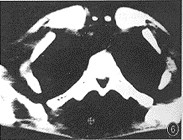

患者男,36岁。腰背部疼痛,颈部不适2个月。因疼痛加重,腰背部出现包块而住院治疗。查体:体温37.5℃,身体消瘦,痛苦病容。T12棘突两侧有直径4cm大小包块,有波动,压痛。T6棘突左侧软组织隆起,压痛。颈部压痛,活动轻度受限,四肢活动及大小便正常。血沉:46mm/h。胸片显示:粟粒型肺结核。颈椎摄片:未见异常。X线片示:T6左侧椎弓根破坏。CT片示:T6左侧椎板、椎弓根骨质破坏,有死骨,且有软组织肿胀影突入椎管(图1)。T12棘突骨质破坏,有死骨,后方皮下有低密度影(图2)。诊断:T6、T12附件结核伴冷脓肿,粟粒型肺结核,颈痛待查。按3HRZS/15HR方案抗痨治疗[1,2](注:H-异烟肼,R-利福平,Z-吡嗪酰胺,S-链霉素)。半个月后,分别行T6和T12经后路结核病灶清除术,清除较多脓液、干酪样物及少量死骨。病理检查:T6、T12结核。术后10余天,颈痛加重,活动受限,吞咽感咽部不适,有发热、出汗,体温38℃。颈椎CT片示:寰椎骨质破坏,有死骨,寰枢关节左右间隙不对称,咽后壁软组织影增宽,食管受压(图3,4)。诊断:寰椎结核伴冷脓肿,寰枢椎半脱位。给予输血、补液等支持治疗后,经口腔行病灶清除术,清除少量脓液、干酪样物及少量死骨。术后继续抗痨治疗,颈托固定。此后,颈痛缓解,精神食欲渐好,血沉降至28mm/h。1个月后,胸前(胸骨柄、双侧第四前肋骨处)、上背部出现包块。胸片显示:粟粒型肺结核,双侧第四前肋内侧骨质破坏(图5)。CT片示:T2棘突骨质破坏消失,有低密度的软组织肿胀影(图6)。诊断:T2棘突结核伴冷脓肿,胸骨柄及双侧第四前肋结核伴冷脓肿。考虑结核杆菌感染未能完全控制,改用3HE1321ThK/21HE1321Th方案[1-3](注:H-异烟肼,E-乙胺丁醇,1321Th-丙硫异烟胺,K-卡那霉素)抗痨治疗半个月后,行病灶清除术,分别清除T2、胸骨及肋骨结核病灶。术后1年随访,患者恢复了日常生活及工作,局部无疼痛,血沉正常,体重由入院时的45kg增加到70kg,再未发现新的结核病灶。

图1CT片显示T6左侧椎板、椎弓根骨质破坏,有死骨,且有软组织肿胀影突入椎管图2CT片显示T12棘突骨质破坏,有死骨,后方皮下有低密度影图3,4CT片显示寰椎骨质破坏,有死骨,寰枢关节左右间隙不对称,咽后壁软组织影增宽,食管受压图5胸片显示粟粒型肺结核,双侧第四前肋内侧骨质破坏图6CT片显示T2棘突骨质破坏消失,有低密度的软组织肿胀影